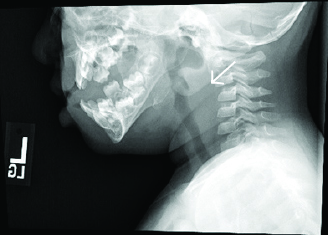

Initial evaluation should include complete blood count and blood culture, although this may be postponed to the operating room if the child’s airway is thought to be tenuous. The white count often will be elevated with bandemia. Blood cultures rarely are positive but are helpful in determining a pathogen. Imaging often begins with a lateral neck radiograph.

When a retropharyngeal infection is present, the prevertebral space will be widened. Prevertebral soft tissues at the level of C3 should measure less than two-thirds of the anteroposterior width of the body of the third cervical vertebra. Alternatively, the retropharyngeal space is considered pathologically widened if it is greater than 7 mm at C2 or 14 mm at C6 in children.26 There often will be loss of the normal cervical lordosis due to spasm of inflammation. In rare cases, an air-fluid level or gas may be seen in the prevertebral area. (See Figure 3.)

Figure 3. Soft Tissue Neck X-Ray in Child with RPA Shows Widening of the Prevertebral Space |

Image courtesy of Derya Caglar, MD. |